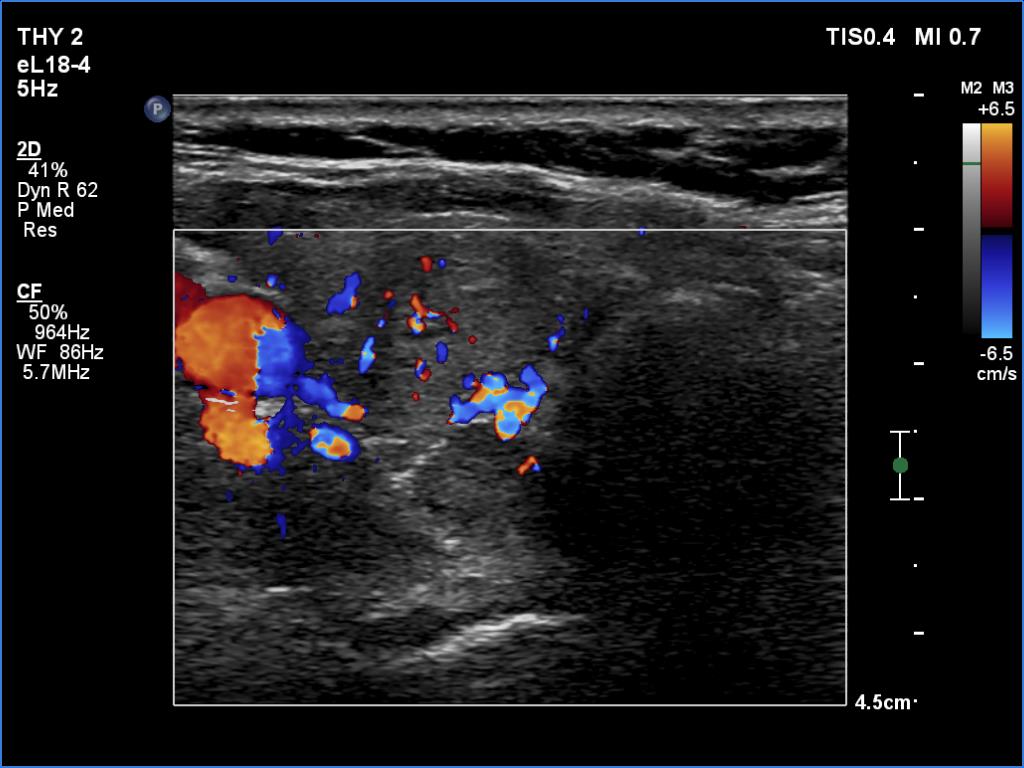

Clinical data: A 61-year-old woman was referred for preoperative localization of a parathyroid adenoma. The patient has been treated for hypothyroidism for seven years. Recently, hyperparathyroidism was diagnosed on evaluation of osteoporosis. MIBI scintigraphy disclosed increased uptake according to one of the left parathyroids.

Ultrasonography. The thyroid was moderately hypoechoic. There were two discrete lesions in the right lobe while a hypoechoic mass was found dorsal to the middle third of the left lobe.